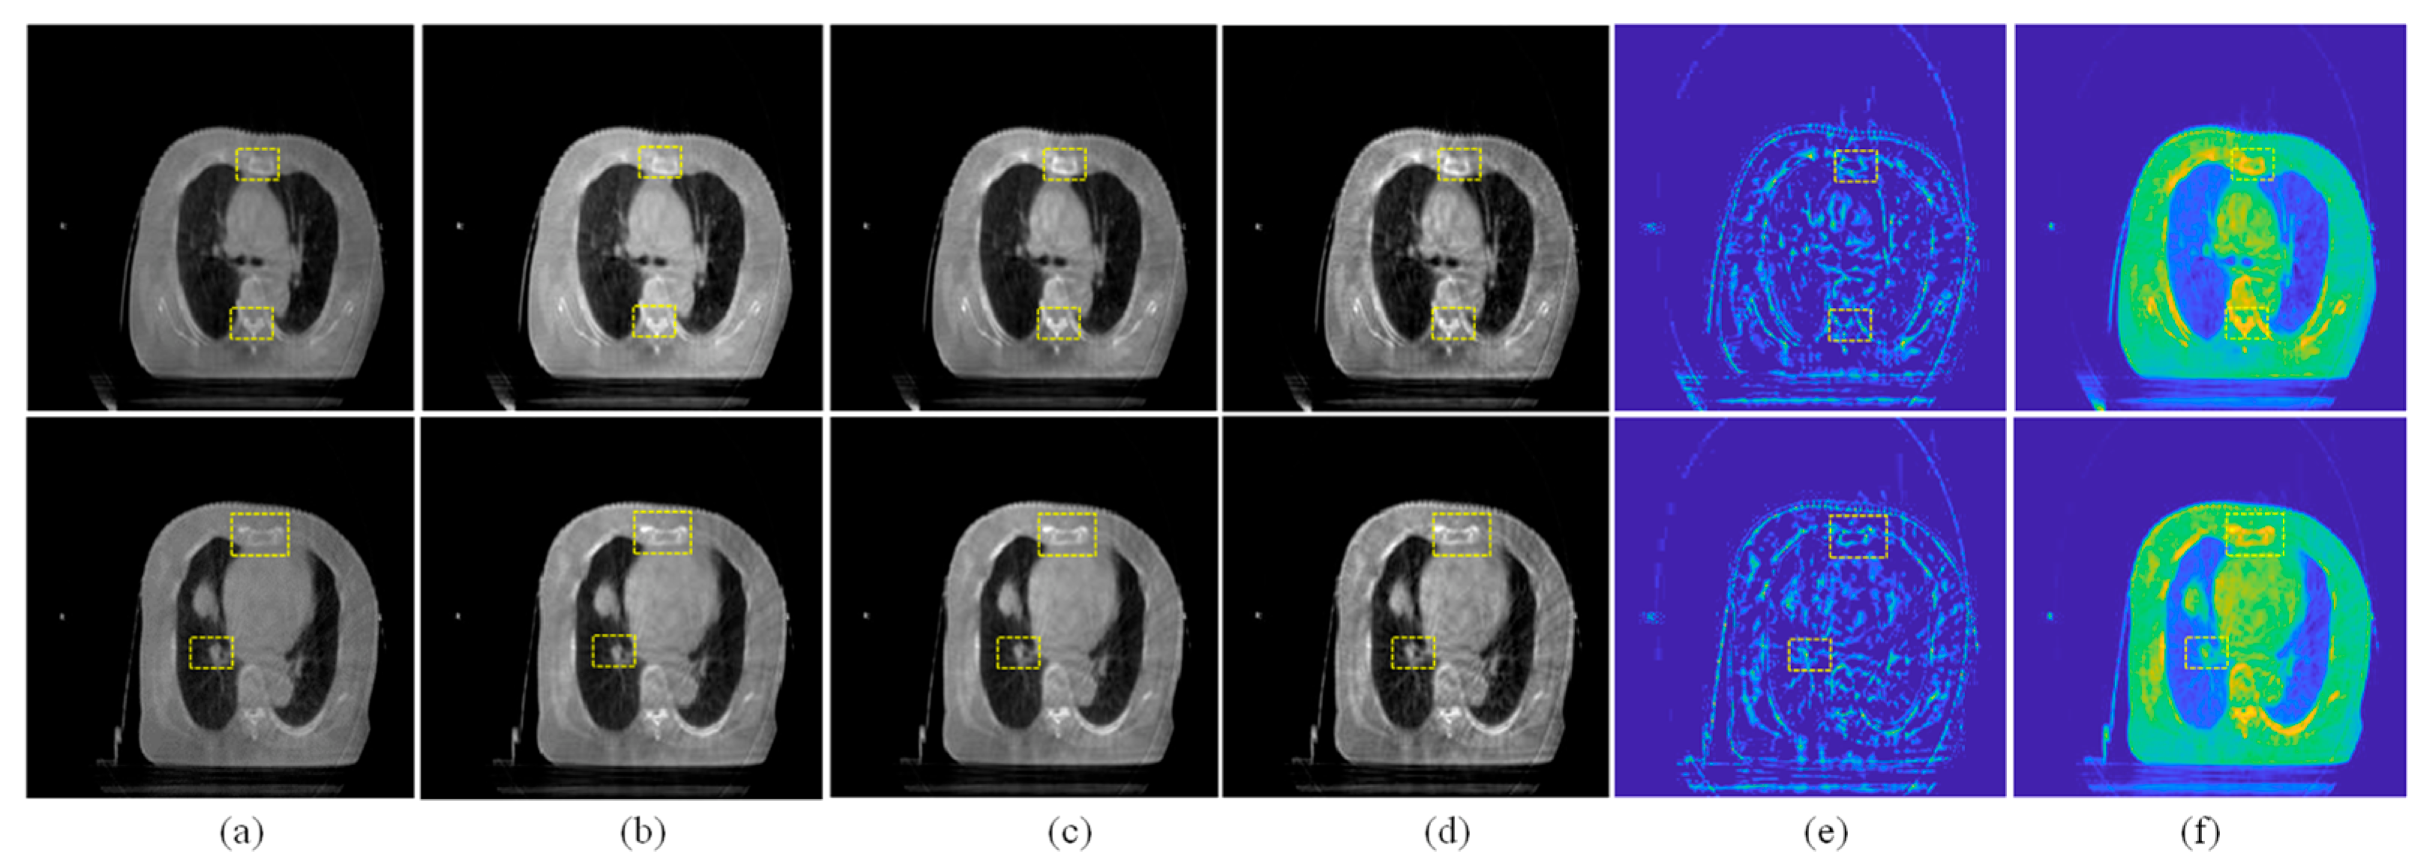

In this section, the registration results between the source CBCT and CT images and between the CBCT images enhanced using different enhanced algorithms and CT images are compared and analyzed. In this experiment, all the registration results are obtained by the same registration model [39]. In addition to visual analysis, we also give the SSIM values before and after the registration of these images to objectively measure the registration performance.

As shown in Figure 12, Figure 12a is the unregistered source CBCT and CT images. The SSIM value of the source images is 0.5532, and it can be seen from Figure 12a that the imaging position and size of the source CBCT and CT images are different. Figure 11b is the registration result by the source CBCT and CT, and the SSIM value is 0.7184 if the CBCT image is used directly for the registration task. In the enlarged image, the edge regions are not exactly aligned in Figure 12b. Except for the CBF enhancement method, the registration accuracy was improved after CBCT images were enhanced by other methods. For example, in Figure 12c, the SSIM value is 0.7486 by registering the MSR-enhanced CBCT and CT images, which shows improved accuracy of non-enhanced CBCT and CT registration. In other words, the enhancement of CBCT images is helpful to improve the registration accuracy of CBCT and CT, which is very critical and meaningful for IGRT.

Figure 12.

Registration comparison. The positions of the two images are shown in different colors. (a) Source CBCT and CT images. (b) Registration results of source CBCT and CT images. (c) Registration results of MSR-enhanced CBCT and CT. (d) Registration results of MSRCR-enhanced CBCT and CT. (e) Registration results of DCP-enhanced CBCT and CT. (f) Registration results of CBF-enhanced CBCT and CT. (g) Registration results of RRM-enhanced CBCT and CT. (h) Registration results of SMIPC-enhanced CBCT and CT. (i) Registration results of CBCT and CT enhanced by our method.

From the yellow arrows, it can be seen that our method’s results have the highest registration accuracy and achieve the best SSIM value of 0.7729. In the enlarged image, it can be seen that the proposed method outperforms the comparison methods in the registration accuracy of the edge regions. This is because the proposed method enhances the saliency features, which plays a key role in the registration process. In addition, since the proposed method includes the denoising step, the noise points on the edges of image that may affect the registration were filtered out, which also helps to improve the registration accuracy.